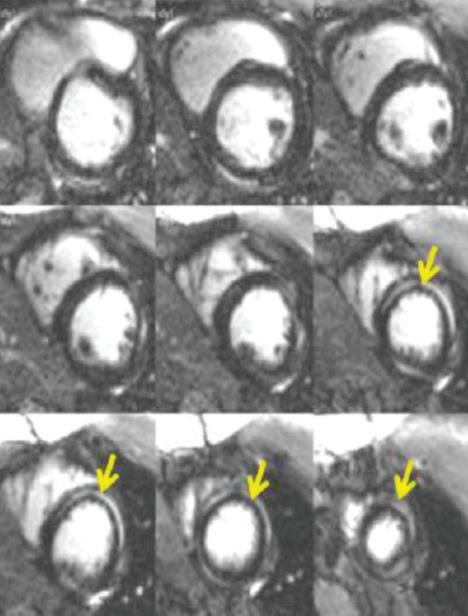

ЯМР е отличен и най-ефикасен неинвазивен диагностичен метод за оценка на тъканната характеристика на миокарда – окачествяване на възпалението, разпространението на миокардна фиброза, което позволява диференциране между активен миокардит срещу възпалителен миокардит. Проблемът е, че

след 4-тата седмица, тъй като интерстициалният оток отзвучава след този период, което рязко намалява възможностите на метода. Възприети са три основни критерия за миокардно възпаление: 1. Сигнал за хиперемия, отразен в ранно гадолиниум натрупване (LGE); 2. Тъканен оток – увеличено миокардно Т2 релаксационно време или увеличен сигнален интензитет в Т2 образите; 3. Наличие на фиброза. Приема се, че ако 2 от тези критерии са

положителни, диагнозата остър миокардит е налице със 74% сензитивност и 86% - специфичност. Наличието на LGE се асоциира с повече от два пъти увеличение на риска за големи сърдечни усложнения – комбинация от смърт, хоспитализации за сърдечна недостатъчност и рецидивиращи камерни аритмии (Фиг. 3).

Септалното и наблюдаваното в средните миокардни сегменти LGE, както и дифузното му разпределение, носят информация за по-тежко протичане на острия миокардит и са най-силния предиктор за по-лош изход. Разпространението на LGE (над 10%) се асоциира със 79% повишен риск за големи сърдечни усложнения (Фиг. 4).